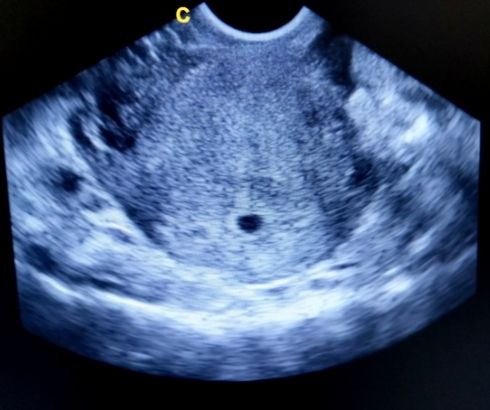

3 Weeks Pregnant Ultrasound

Doctors in most countries perform the first pregnancy scan between 8 and 14 weeks. Ultrasound is not prescribed unless it is necessary. Most ultrasound devices will not even be able to show a fetal egg. It is still too small and requires considerable experience and high-precision equipment to determine it.

Few things can be determined by ultrasound in such a short time. The exact details of the pregnancy are yet to be seen. There are only a few points that allow us to conclude the condition of a woman. Ultrasound is prescribed if a woman had complaints of well-being, poor discharge, or pain.

Based on the results of the examination, the doctor can determine:

- Fertilized egg

- The state of the endometrium of the uterus

- Absence of ectopic pregnancy

- Absence of pathologies in the uterus

It is not yet possible to give any more precise details regarding the development of the fetus. Examination by ultrasound at this time is unjustified.